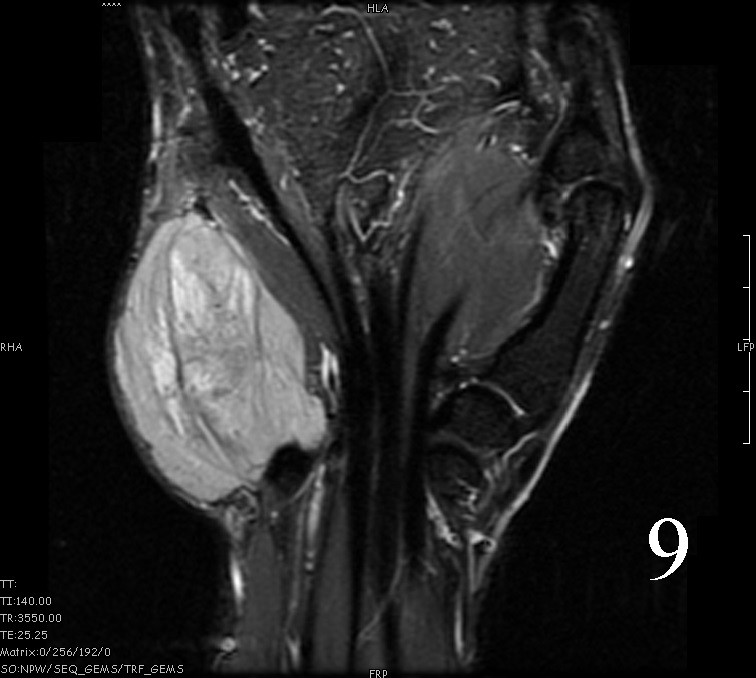

MRI

- Heterogeneous mass (does not follow signal of skeletal muscle)

- Isointense to skeletal muscle on T1 (Fig. 4, Fig. 5, Fig. 7, Fig. 8)

- Hyperintense signal on T2, sometimes low to intermediate signal on T2 if there is extensive fibrous tissue within the tumor (Fig. 6, Fig. 9).

- Prominent vascularity

- Deep enhancement with gadolinium

- Possible extensive hypercellular fibrous tissue and hemosiderin seen on T2

Fig. 4-9: MRI of a rhabdomyosarcoma of the hand. The MRI is nonspecific and shows a heterogeneous mass particularly on postgadolinium images T1 W images (Fig. 8) and T2 W images (Fig. 9).